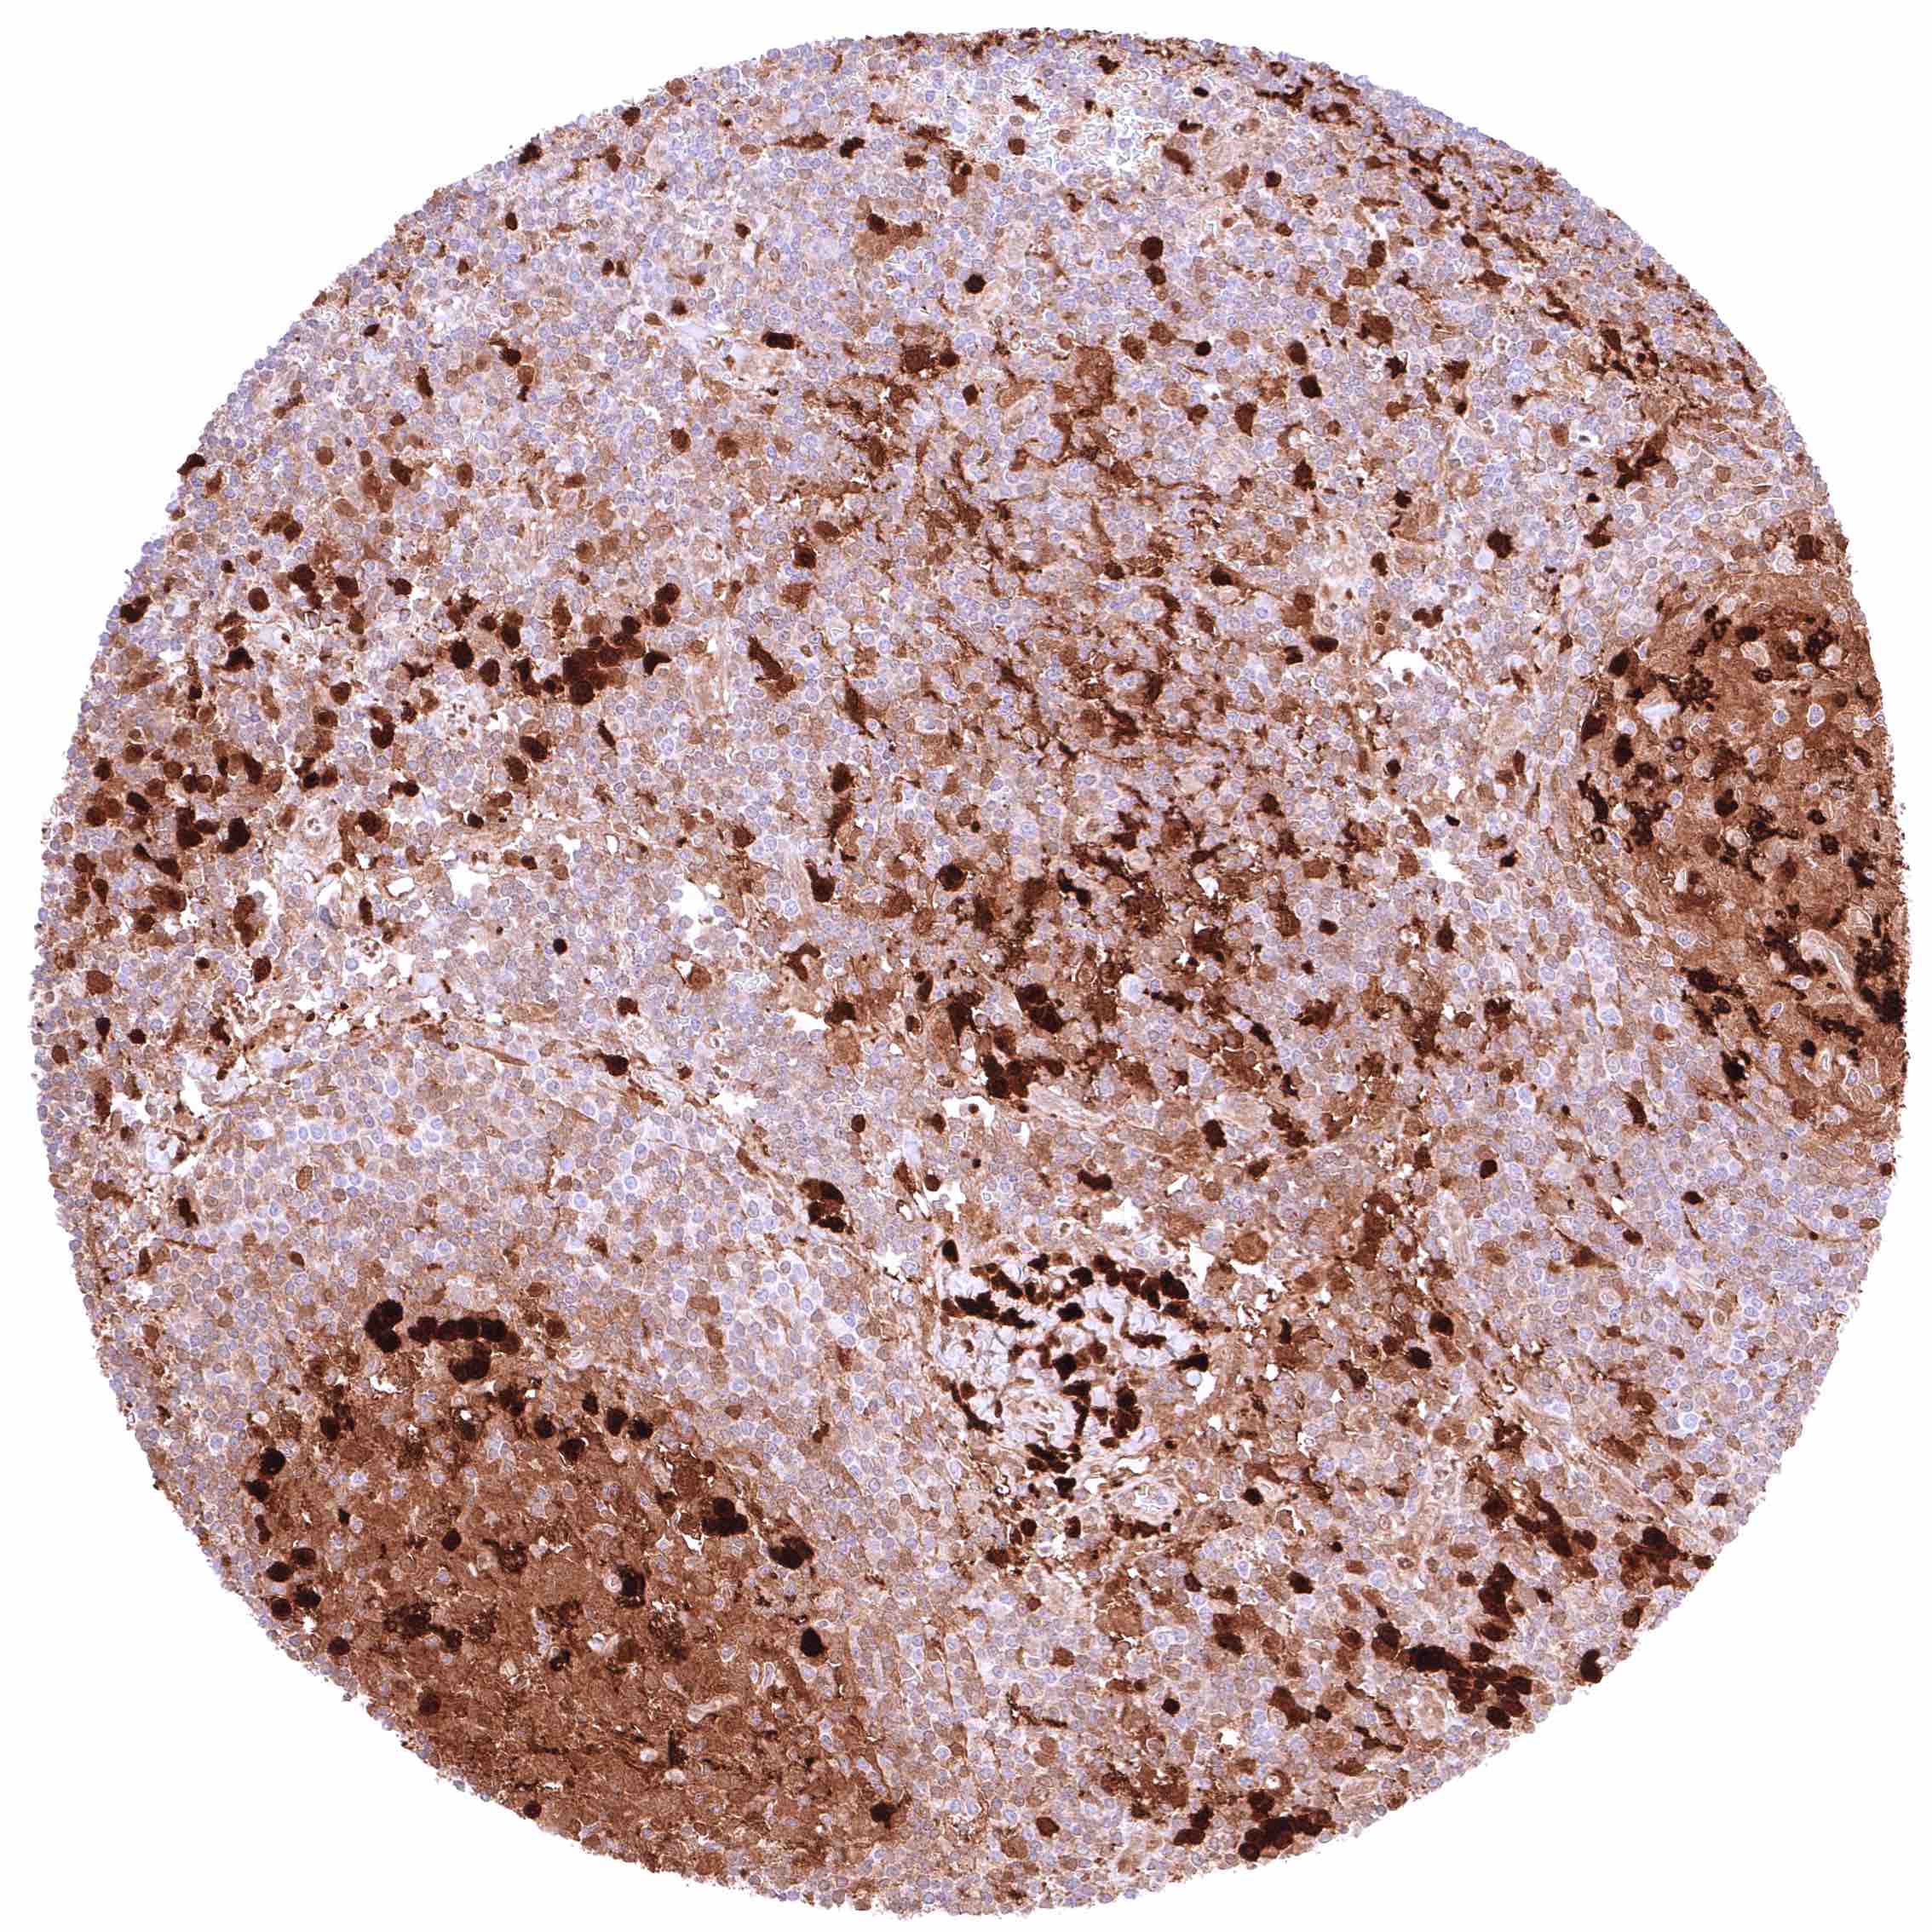

Bone marrow – Moderate to strong, nuclear and cytoplasmic GSTP1 staining of most cell populations although some cell types (erythropoiesis_) remain GSTP1 negative